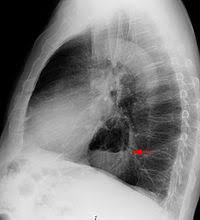

90 Prozent der Betroffenen der Refluxkrankheit leiden zusätzlich an einem Zwerchfellbruch axiale Hiatushernie. Eine klinische Bedeutung erlangt die Hiatushernie erst dann wenn sie mit einer Refluxösophagitis assoziiert ist. Vor allem wenn die Refluxösophagitis durch einen Zwerchfellbruch Hiatushernie verursacht wird kann eine Operation jedoch von Vorteil sein.

Eine Behandlung der Hiatushernie ist höchstens chirurgisch möglich. Das Zwerchfell ist ein großer Atemmuskel der den Brustkorb vom Bauchraum trennt. Ursachen von Reflux - GERD können ein funktionsgestörter strukturell defekter inkompetenter unterer Speiseröhrenschließmuskel sein - meist auf Basis einer Hiatushernie Zwerchfellbruch - eine primäre Störung in der Bewegung der Speiseröhre oder aber auch eine gestörte Magenentleerung um die wichtigsten Ursachen zu nennen.

Die drei Öffnungen für die Speiseröhre die Hauptschlagader Aorta und die Hohlvene Vena Cava sind natürliche Schwachstellen des Muskels. Übliche Symptome sind Sodbrennen Reflux sowie Schmerzen oder Schwierigkeiten beim Schlucken. Das Leitsymptom bei einer Entzündung der Speiseröhrenschleimhaut Refluxösophagitis ist Sodbrennen.

Das ist schmerzhaft weil der Mageninhalt sehr sauer ist und brennt. Auch mögliche Durchblutungsstörungen können Schmerzen auslösen.